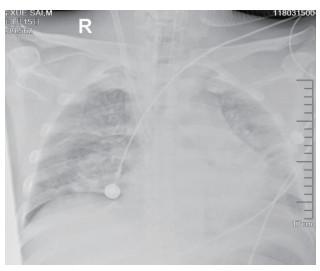

该患者入院后因氧合不能维持、呼吸窘迫直接从急诊收治ICU,大剂量激素冲击及气管插管,呼吸机SIMV+PS模式支持治疗,氧合指数改善不明显,及时行俯卧位通气,但氧合指数仍然小于100,PAO2 38 mmHg, SpO2 78%左右,考虑患者病情危重,且血流动力学不稳,血管活性药剂量大,当天下午行V-V模式ECMO治疗(右侧颈静脉-右侧股静脉),血流速度3.5 L/min,氧流量3.5 L/min,氧体积分数50%,行保护性机械通气,通气模式是压力控制(PC 15 cmH2O,PEEP 8 cmH2O,FiO2 50%,f 12次/min), 镇痛镇静,RASS评分在-4~-5分,必要时阿曲库铵静脉推注行肌肉松弛治疗。其他治疗:甲强龙500 mg治疗3 d,然后逐渐减量;乙酰半胱氨酸抗氧化、化痰、CRRT等支持治疗。ECMO治疗后生命体征明显改善,治疗第2天,血管活性药逐渐减量。治疗3 d后,循环稳定,停用血管活性药,床旁胸片提示:两肺弥漫渗出性改变,较前明显好转。患者症状好转,调节ECMO参数:血流速3 L/min,气体流速3 L/min,氧体积分数35%,控制SpO2 95%~100%之间。在ECMO治疗期间根据血流动力学和血气分析结果不断调整ECMO参数,在ECMO治疗5 d后,脱离ECMO,通气模式改为SIMV+PSV并过渡到PSV(PS 16 cmH2O,PEEP 5 cmH2O,FiO2 30%),氧合良好,在脱离ECMO 2 d后停呼吸机,停机1 d后拔除气管插管。行胸部CT检查示:两肺散在炎性病变,双侧胸膜腔积液(图 3),床旁胸片提示两肺炎性病变(图 4),两肺弥漫性渗出明显改善。后经1周治疗,查胸部CT示:右肺中下叶及左肺少许慢性炎性改变(图 5),病情稳定转至呼吸科病房。

| 图 3 3月16日胸部CT |